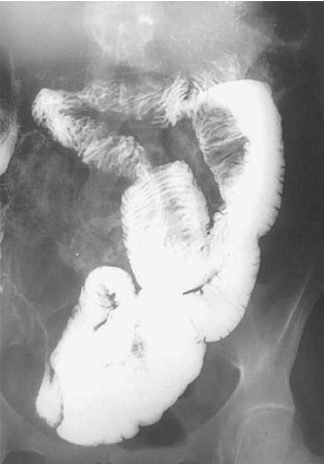

Homem de 16 anos, pardo, procurou o ProntoSocorro com queixa de dor abdominal há uma semana. Duas semanas antes da consulta, tinha apresentado quadro de dor abdominal difusa, em cólica, de grande intensidade, que cedeu ao antiespasmódico aplicado em outro serviço. Passou uma semana apresentando dores leves, esporádicas. Na semana anterior, a dor voltou e como não apresentou melhora com a mesma medicação utilizada no primeiro episódio, buscou atendimento médico. Referia dois episódios de vômitos no dia da consulta, com saída de sangue na evacuação diarreica. Negava febre, negava história de dor abdominal anterior à relacionada a esta consulta, negava comorbidades. Ao exame físico abdominal apresentava dor à palpação profunda de fossa ilíaca direita, dor à descompressão brusca abdominal, sem visceromegalias, sem massas ou tumorações palpáveis. Uma peculiaridade do exame era que, à palpação da fossa ilíaca direita, não se palpavam alças. Exames laboratoriais e radiografias abdominais não mostraram alterações. Foi internado para investigação diagnóstica e submetido a exame contrastado (demonstrado na imagem). O diagnóstico do paciente é:

Enunciado 4099942-1

(Fonte: Dr. Melvyn H. Schreiber, The University of Texas Medical Branch, Galveston, TX)